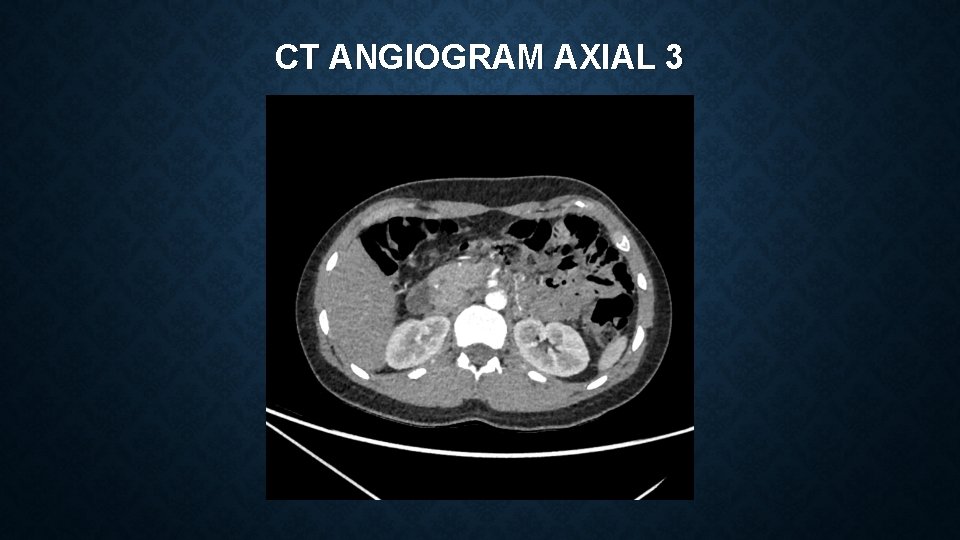

CT ANGIOGRAM AXIAL 3

MEDIAN ARCUATE LIGAMENT SYNDROME Vague constellation of symptoms which can include : • epigastric pain, postprandial pain, chronic non-specific abdominal pain, nausea, vomiting, weight loss Often a diagnosis of exclusion – reliant on clinical features and imaging findings Investigations include – CT angiogram and duplex ultrasonography CT – focal narrowing of coeliac artery with post-stenotic dilatation USS – Peak systolic velocities of >200 cm/s are suggestive of MALS